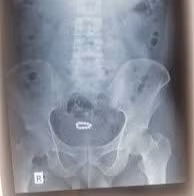

Qua thăm khám ban đầu và các chẩn đoán hình ảnh (X-quang, siêu âm), đội ngũ bác sĩ đã phát hiện một dị vật có hình dạng vòng tròn, nằm gọn trong lòng bàng quang.

Với trường hợp bệnh nhân 32 tuổi này, dị vật là một chuỗi hạt kim loại nhiều màu sắc. Bệnh nhân đã tự ý đưa chuỗi hạt vào niệu đạo với mục đích kích thích và tạo cảm giác lạ. Tuy nhiên, do cấu trúc niệu đạo nam giới khá dài và ngoằn ngoèo, chuỗi hạt đã bị mắc kẹt và không thể tự lấy ra.

Hình ảnh dị vật trên phim chụp và sau khi được lấy ra - Ảnh BVCC